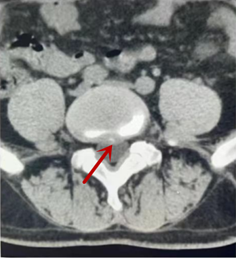

箭頭提示椎間盤突出

從左向右依次為CT矢狀位重建圖像、三維重建圖像、軸位掃描圖像,箭頭提示腰1椎體爆裂性骨折